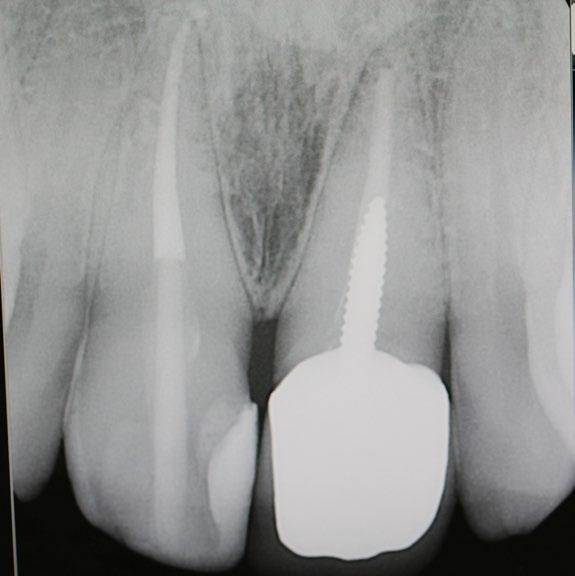

What are Dental Implants?

Dental implants are titanium posts surgically inserted into the jawbone, where they serve as a sturdy anchor for replacement teeth. Unlike dentures or bridges, which rest on top of the gums, implants integrate with the bone, a process known as osseointegration. This integration stabilizes the implant and makes it a permanent fixture in the mouth. The result is a replacement tooth that looks, feels, and functions like a natural tooth.

Creating a New Look with Dental Implants

One of the most significant advantages of dental implants is their ability to restore a natural-looking smile. They are customdesigned to match the natural color and shape of the patient’s existing teeth, blending seamlessly into the mouth. This can dramatically improve a person’s appearance, making them look younger and healthier. For many, this can lead to a renewed sense of self-esteem and vitality, particularly important as they age.

Implants act like natural tooth roots, promoting bone growth and preventing bone loss. Maintaining this bone structure not only supports facial features but also prevents the aging appearance that often accompanies tooth loss.

Long-Term Benefits and Oral Health

Dental implants also contribute positively to long-term oral health. They help preserve the jawbone and maintain the integrity of facial structures. When teeth are lost, the jawbone can gradually deteriorate because there is no tooth root to stimulate bone growth.

Moreover, unlike bridges and dentures, which often require the reduction of other healthy teeth to accommodate the appliance, implants do not compromise the health of neighboring teeth. This preservation of natural teeth is crucial for maintaining longterm dental health.